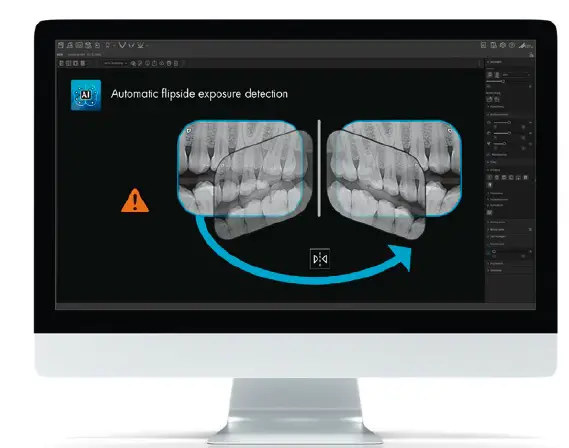

Wrong-side exposure detection

VistaSoft AI automatically detects potential cases where the image plate has been exposed on the wrong side and informs the user accordingly.

Website